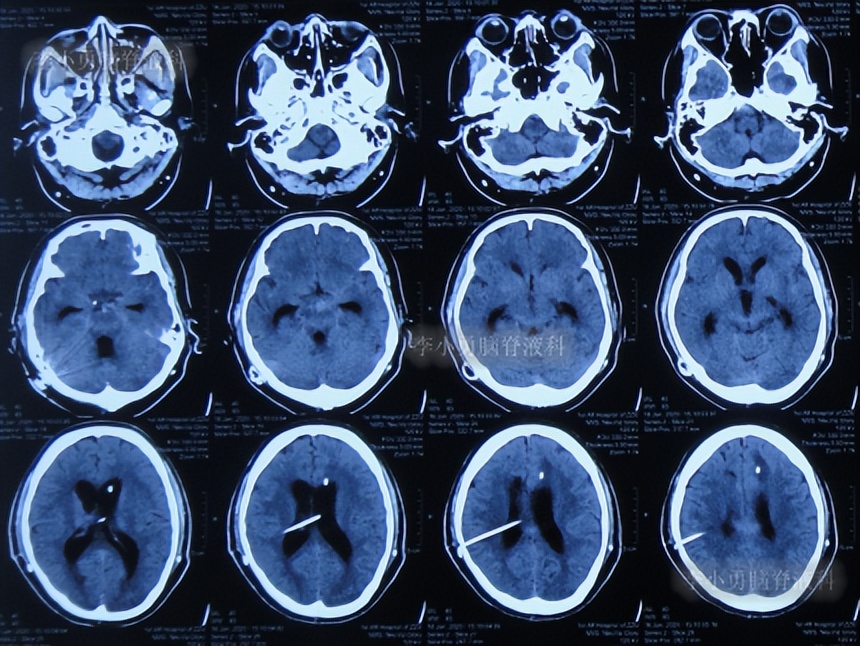

半月后即2022年6月17日,第3次住入李小勇脑脊液科,入院时:进食差,言语混乱,记忆力差,行走差(图-52);查头颅CT示右侧颞角增大,四脑室也稍大(图-53);肺部CT有感染(图-54)。

图-53:入院时头颅CT

2022年6月20日(入院后3天),进行了脑室腹壁外引流术,术前术后头颅CT对比(图-55)。

图-55:2022年6月20日术前术后头颅CT

2022年6月23日(入院治疗6天),查头颅CT示脑室周有水肿(图-56)。

图-56:2022年6月23 日头颅CT

2022年10月7日(入院治疗112天),查头颅CT示脑室周水肿消失,脑室变小(图-57)。

图-57:2022年10月7日头颅CT